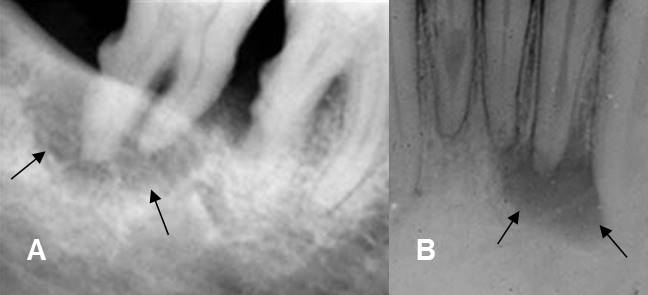

Fig 41. Enfermedad periododontal.

A y B: Rx periapical. Incremento del espacio periodontal, con lucencia que rodea las

raíces dentales y corresponde a bolsa periodontal.